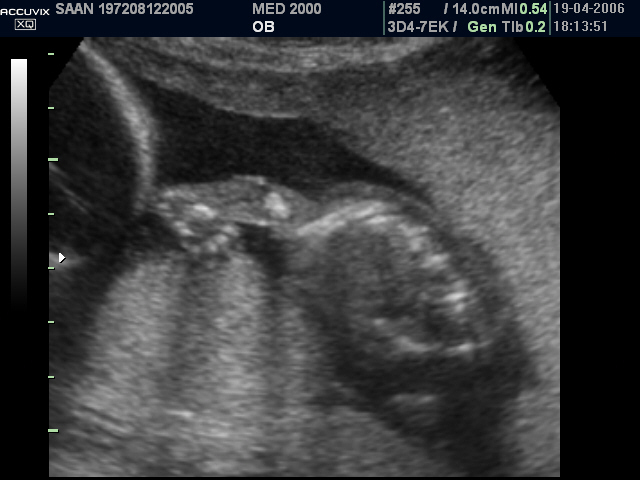

Le anomalie scheletriche più comuni sono le anomalie del raggio radiale: ipoplasia o aplasia del radio, pollice a tre falangi, mano torta, a volte assenza del pollice.